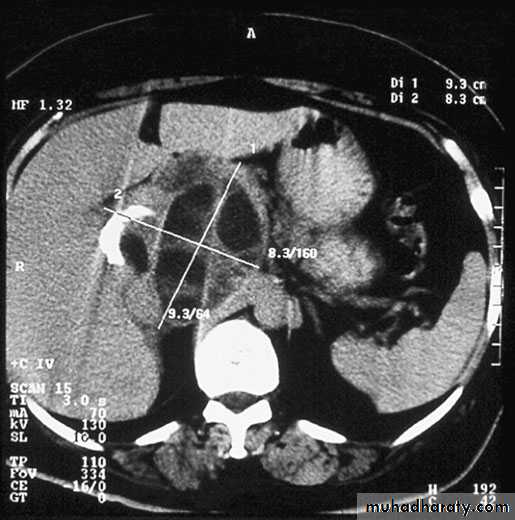

Ultrasound and CT scan are the investigations of choice. The CT scan shows a smooth space-occupying lesion with several septa .An ultrasound of the biliary tract may show abnormality in thegall bladder and bile ducts. Hydatid infestation of the biliary system should then be suspected.